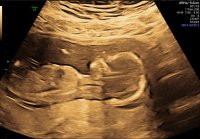

I dag har vi hilset på en frisk og fin liten lillebror :Heartblue ble satt frem en dag, så er 13+6 i dag :)

Ny tidlig ultralyd i dag, 13+6. Vi fikk vite at vi venter en liten gutt! :Heartblue :joyful: